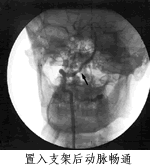

本报讯 (驻地记者 匡远深)北京天坛医院放射科主任医师姜卫剑等采用血管内支架技术,治疗椎基底动脉供血不足获得成功,半年间完成手术10例,无死亡、无并发症。

在姜卫剑治疗的10例患者中,还为2例施行颅内动脉支架术。近日随访显示,这10例患者术后无一死亡及并发症,手术成功率达100%。, http://www.100md.com